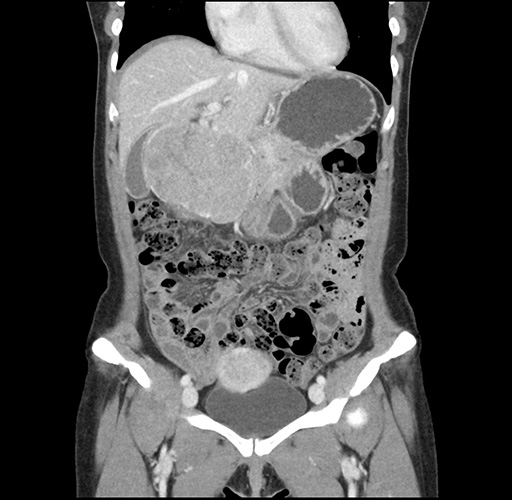

Imaging Analysis

Look through the patient's CT scan to identify any areas of concern for the necessary procedure.

Based on your CT findings, which issue(s) would give reason for "planned slowing down moment(s)" in this case?

Considering a standard left lateral sectionectomy procedure, what step(s) of the operation would you do differently in this case ?